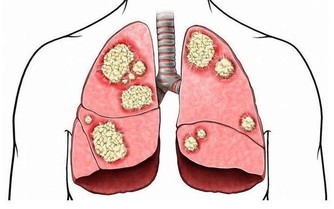

4、誘發冠心病。

尿酸是冠心病死亡獨立危險因素:有研究顯示,無論性別,尿酸是普通人群冠心病死亡的獨立危險因素。血尿酸每升高1mg/dl,死亡危險性在男性增高48%,女性增高126%。血尿酸>357μmol/L是冠心病的獨立危險因素;血尿酸>416.5μmol/L是腦卒中的獨立危險因素。